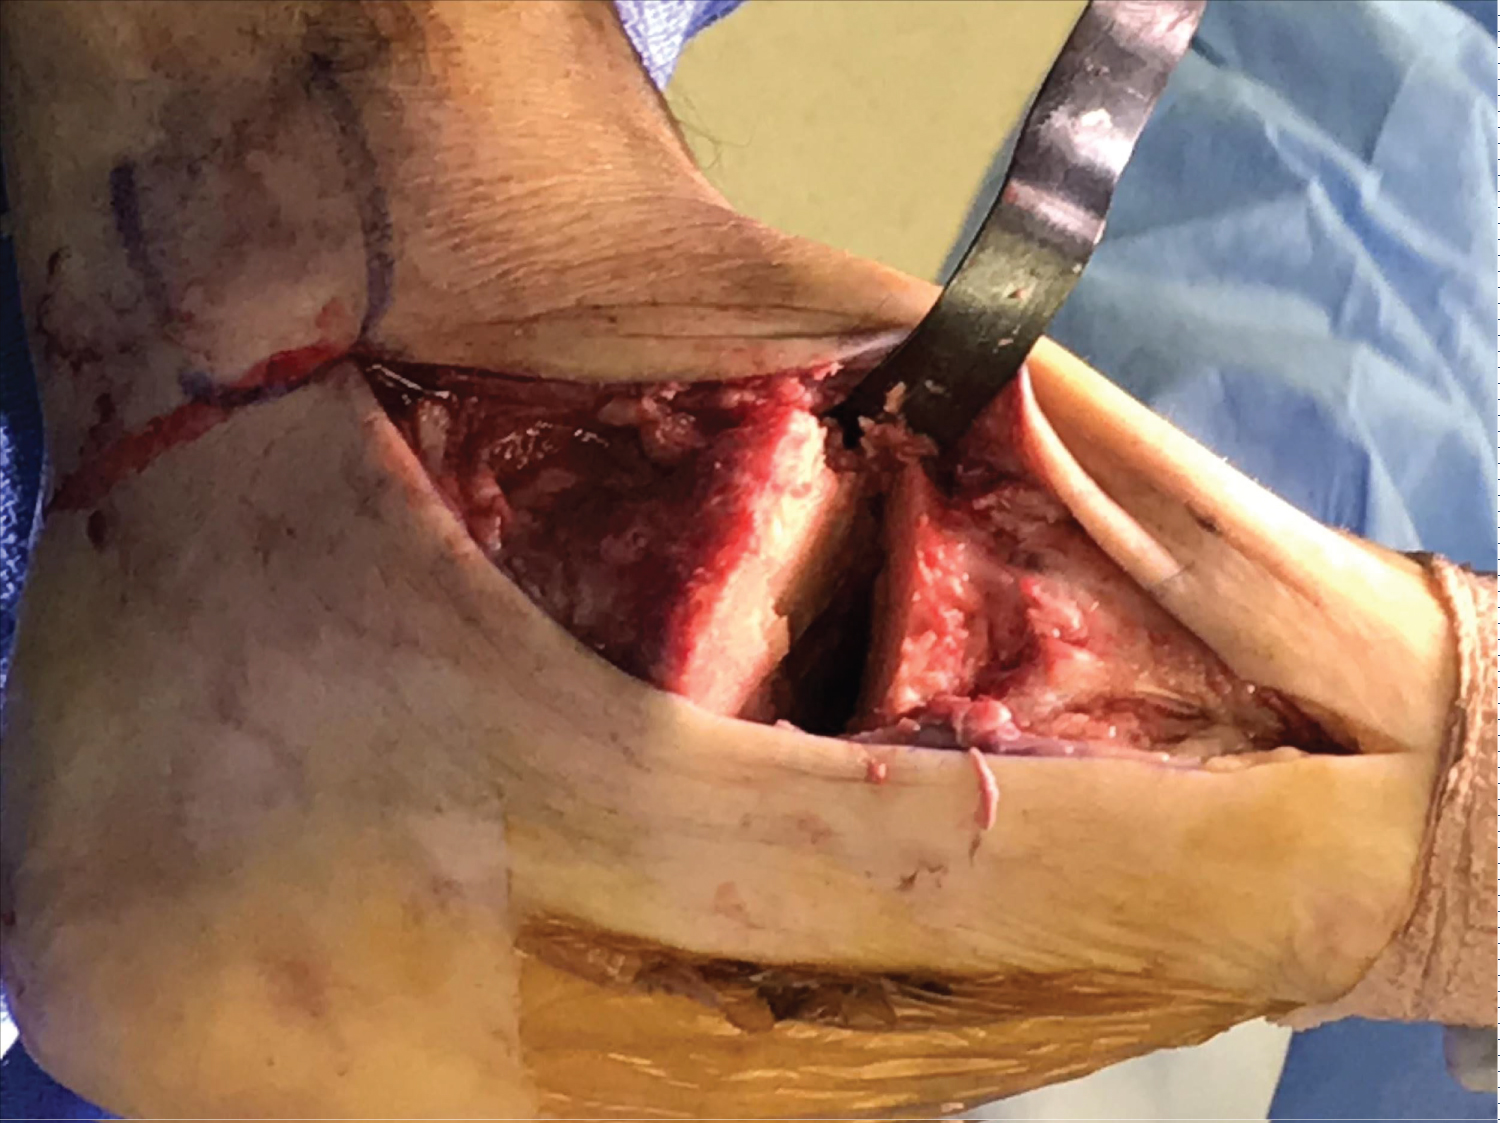

At the time of surgery, the patient is positioned supine on the table. Medial and lateral incisions are made and full-thickness flaps are raised from the bone both dorsal and plantar. Once the soft tissues are raised, a malleable retractor is placed deep to the dorsal soft tissues and another deep to the plantar tissues (Figure 3). This protects the soft tissues during placement of the cut guide and osteotomy.

Figure 3: Cut guide intra-op. View Figure 3